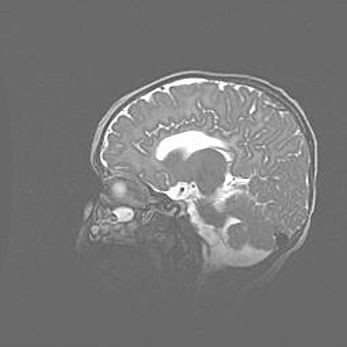

Лейкомаляция с кистозно-глиозной дегенерацией головного мозга.

Возраст: 2 месяца 25 дней

Вес: 6400 г

Окружность головы: 40 см

Срок гестации: 41 неделя

Лейкомаляцию относят к ишемически-гипоксическим повреждениям головного мозга, диагностируемым у новорожденных. При лейкомаляции в головном мозге обнаруживают очаги некроза, возникшие после тяжелой гипоксии и нарушения кровотока. В процессе морфогенеза очаги проходят три стадии: 1) развития некроза, 2) резорбции и 3) формирования глиозного рубца или кисты. Перивентрикулярная лейкомаляция (ПЛ) встречается примерно в 12% случаев среди новорожденных, обычно – у недоношенных детей, причем, частота ее зависит от массы, с которой младенец появился на свет. Наибольшее число малышей страдает лейкомаляцией, если масса при рождении 1500-2500 г.